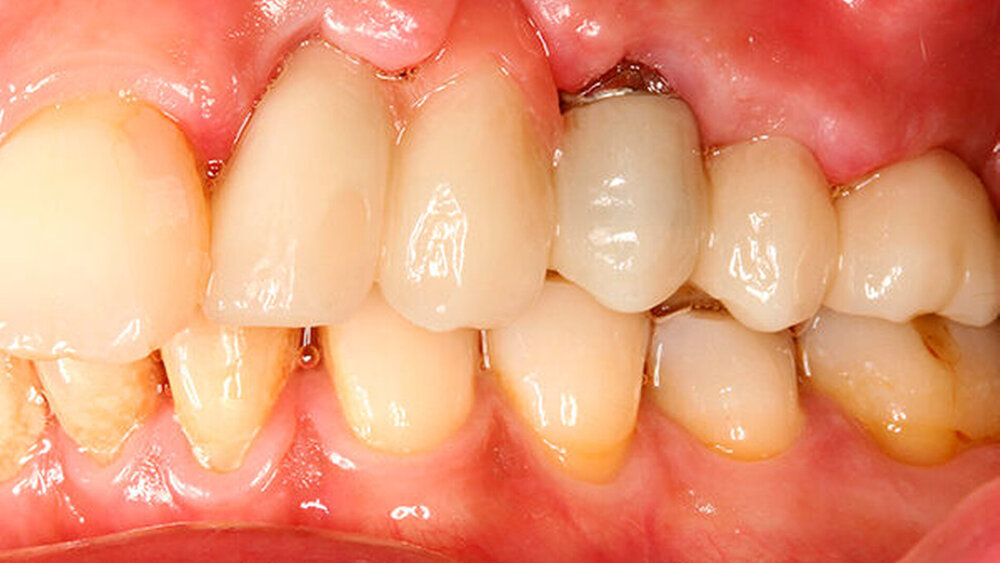

Ich auch, entsprechend konservativ sieht unser Konzept aus, nach dem ich auch meine Frau behandeln würde. Ich ziehe den nicht erhaltungswürdigen Zahn, lege Kollagen ein, kein KEM, um das Blutkoagulum zu stützen. Nach sechs Wochen setze ich entsprechend den prothetischen Rahmenbedingungen im Frontzahnbereich das Implantat und nach zwölf Wochen im Seitenzahnbereich. Die bukkale Lamelle stabilisiere ich mit einem resorptionsstabilen KEM. Dann erfolgt die Abdeckung mit einer Membran (GBR). Für dieses Vorgehen gibt es sehr schöne Zehnjahresergebnisse von Chappuis et al. aus der Berner Arbeitsgruppe, die letztes Jahr veröffentlicht wurden. Für diese Indikation würde ich auch ein BLX verwenden.